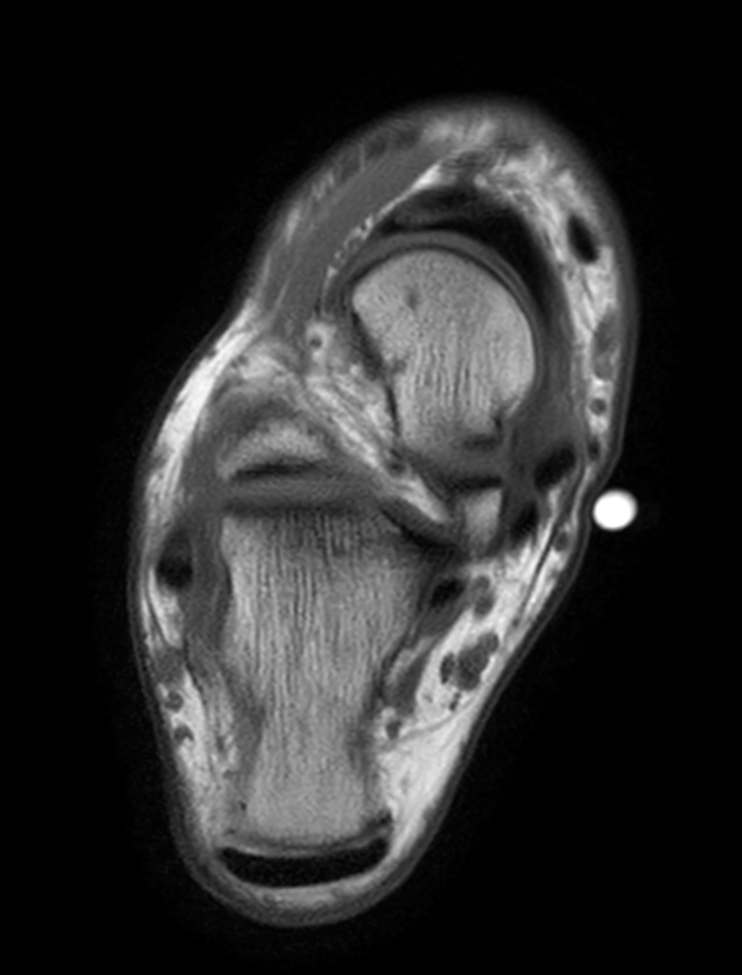

Axial T1w TSE

Axial T2w TSE